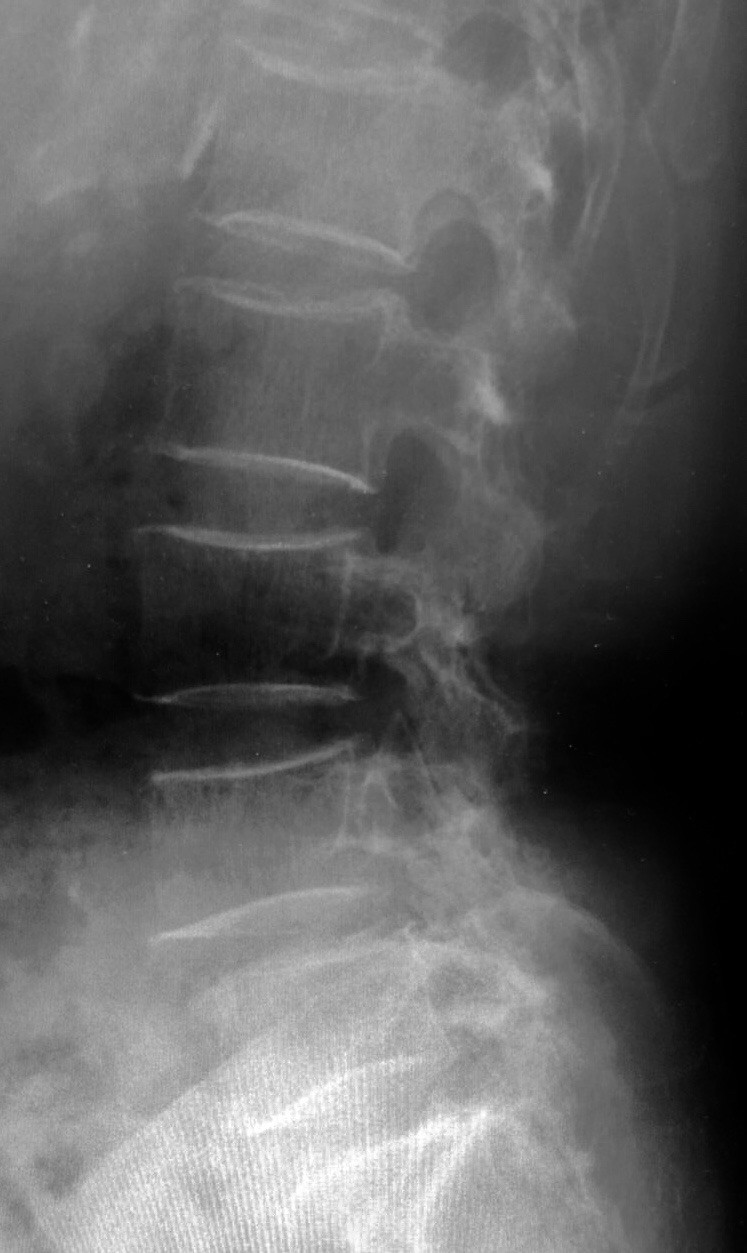

2018/04/16 1年半の間 脊柱管狭窄 と診断されていた

70+α歳 女性。主訴は右大腿部痛による歩行障害。1年半前に、某病院整形外科受診。

腰部脊柱管狭窄と診断。8週間おきに通院、投薬を受けていました。

痛くて、歩くこともままならなくなり、友人に相談。この友人から当院を紹介され受診。腰椎のレントゲン写真が最初の写真。入室時の“典型的跛行”を見れば、診断は容易。

ま・・・、前医で脊柱管狭窄と言われてしまっては、腰椎のレントゲン撮影も無視できず。

腰椎の写真と・・・両股関節正面を撮影。以下が股関節の写真。

両股関節正面。むかって、左側が右の股関節。左股関節と違うのがわかると思います。

右股関節は典型的な関節症性変化を呈しています。

診断は『右変形性股関節症』。

どこから、腰部脊柱管狭窄と言う診断になるのか?問診からも、画像からも、その答えに到達できませんでした。

全く効果を認められていない前医の薬剤は中止。この患者さんの現在の歩容を見たら、迷うことなく、第1選択はオペでしょう。

情報提供書を書きました。歩き方。重要ですね。アルツハイマー型認知症の患者さんが正常圧水頭症を併発していたのも、教えてくれたのは・・・歩き方でした。整形外科領域は画像が命。でも、身体学的所見も無視で、股関節のレントゲンも撮影していなければ、永遠に正解は出せません。1年半なら、良かったのでしょうか?

70+α歳 女性。主訴は右大腿部痛による歩行障害。1年半前に、某病院整形外科受診。腰部脊柱管狭窄と診断。8週間おきに通院、投薬を受けていました。

診断は『右変形性股関節症』。どこから、腰部脊柱管狭窄と言う診断になるのか?問診からも、画像からも、その答えに到達できませんでした。